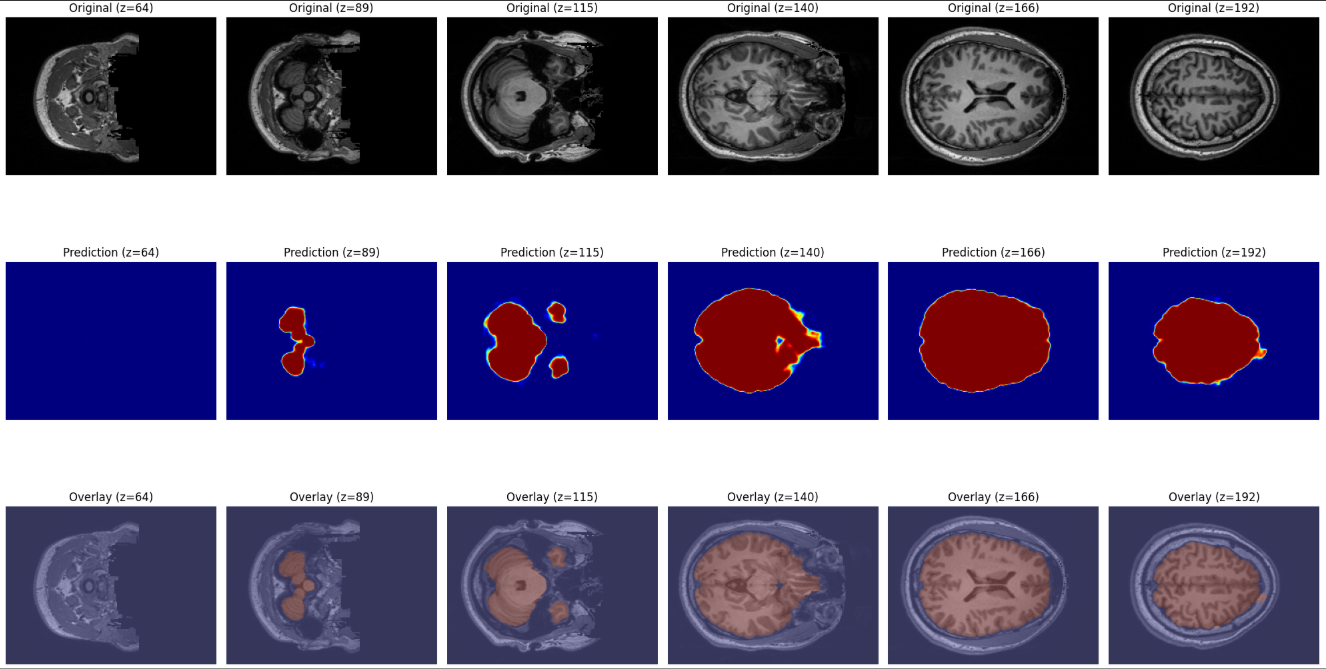

推論フェーズでは、まず学習済みのモデルをロードし、新しい被験者の T1 強調 MRI 画像を入力として与えます。画像は三次元のボリュームデータであるため、学習時と同様に Z 軸方向に沿った二次元スライスへと分割し、それぞれをモデルに入力します。これにより、各スライスに対して脳領域である確率が画素単位で出力され、全体として三次元的な脳マスクを推定することが可能になります。

モデルの出力は連続値の確率分布であり、そのままでは利用が難しいため、一般的な二値化処理を行います。具体的には、確率が 0.5 以上であれば脳領域、未満であれば背景とみなし、最終的に 0 と 1 からなるバイナリマスクを作成します。この閾値処理は単純ながら実用的であり、学習時に用いた損失関数とも整合しています。

得られた予測結果は、可視化によって直感的に確認できるようにします。具体的には、元の T1w 画像に加え、モデルが出力した確率マップ、そして予測マスクをオーバーレイした画像を並べて表示します。これにより、推定された脳領域がどの程度正確に実際の脳構造と一致しているのかを、研究者自身の目で検証することができます。

複数スライスの可視化(オプション)

推論の結果を確認する際には、一枚のスライスだけを可視化するよりも、連続した複数のスライスを並べて表示する方が有効です。特に脳 MRI のような三次元ボリュームデータでは、空間的な連続性が重要な意味を持ちます。中心付近のスライスをいくつか選び、元の画像と予測マスクを横に並べることで、モデルが隣接する断面に対しても一貫した推論を行えているかを直感的に確認できます。

このような可視化は、単に予測の正否を判断するだけでなく、モデルの安定性を評価する上でも役立ちます。もしあるスライスだけマスクがずれていたり、脳領域の形が不自然に途切れていた場合、それは学習データの偏りやモデルの汎化性能の不足を示す可能性があります。一方で、連続するスライスにおいて脳領域が滑らかに再現されていれば、モデルがボリューム全体の構造を捉えている証拠となります。

また、この方法は研究者自身が直感的に異常を見つけるための「品質保証」の手段としても機能します。数値評価指標では見落とされるような局所的なエラーも、複数スライスを俯瞰することで把握しやすくなります。そのため、推論の信頼性を高めるための補助的なステップとして、複数スライスの可視化は非常に有用です。